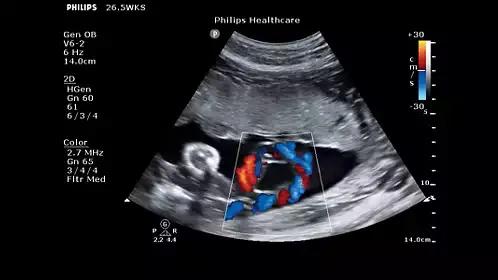

AutoSCAN。OB 启动捷键可一键启动常用的 OB 测量功能。

ClearVue 850提供了例如脉冲反相谐波成像、SonoCT、XRES等众多的成像技术,保证在日常工作中医生能够轻松获得高品质的诊断图像,同时也提供了全方面的高等级成像功能,例如:FloVue高分辨率灰阶血流成像,FloVue利用飞利浦在多普勒信号处理技术和能量成像技术领域的丰富经验,提供了一个全新的血流成像模式。它不依赖靠取样角度的偏转,也不依赖探测速度范围的调整,可以明显提升对微细血管的血流显示能力,并且对大血管的血管壁成像及管壁斑块的诊断有着极其有效的帮助。

ClearVue850提供了颈部血管内中膜厚度(IMT)自动测量,ClearVue850利用二维图像所获得的数据,可自动描绘并记录IMT数值,可有效避免人为误差因素,可快速、准确的对颈动脉的内膜厚度及颈动脉斑块进行判别诊断。当然,常用测量工具如:解剖M型,组织多普勒,辛普森测量,产科胎龄,胎重,血管频谱自动描计测量等也都具备。

AutoSCAN 可以在扫描过程中进行动态优化,从而提供的图像质量。曲面取样技术 (Curved ROI) 和胎儿面部自动识别 (Auto Face Reveal) 提供了 30 种**的编辑工具,专门用于提高 OB 工作效率。负荷*声心动图实现心脏负荷检查标准化。